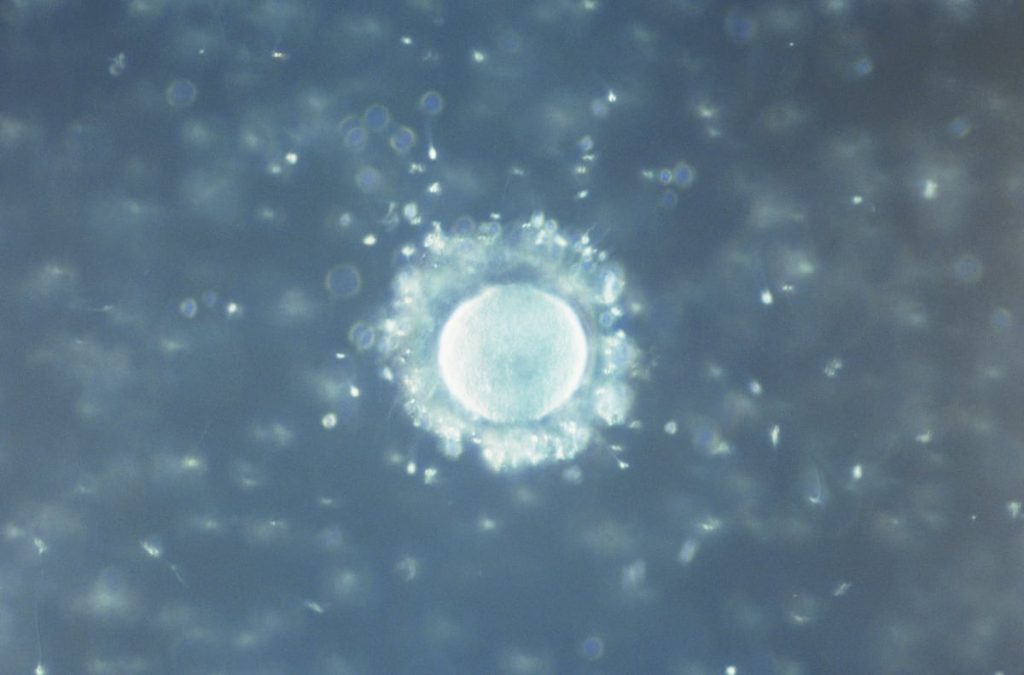

Les analyses des échantillons de sperme et de fluide foliculaire révèlent des taux élevés de contamination par des microplastiques. Bien que les résultats soient surprenants, ils suggèrent que ces déchets sont présents dans de nombreux autres organes et tissus. Cependant, leur abondance dans les fluides reproductifs représente un nouveau défi sanitaire et environnemental.

Des chercheurs de l’Université de Murcie, en collaboration avec des cliniques de reproduction assistée, ont détecté des microplastiques dans 69 % des échantillons de fluide foliculaire chez les femmes et dans 55 % des échantillons masculins analysés. Ces fluides sont essentiels tant pour la conception naturelle que pour les traitements de fertilité. Le polymère le plus répertorié est le polytétrafluoroéthylène (PTFE), connu commercialement sous le nom de Teflon, trouvé dans 31 % des échantillons féminins et 41 % des échantillons masculins. D’autres plastiques courants tels que le polystyrène (PS), le téréphtalate de polyéthylène (PET), la polyamide (PA), le polypropylène (PP) et le polyuréthane (PU) ont également été identifiés.

Les chercheurs ont utilisé des récipients en verre pour stocker les échantillons et ont appliqué des techniques d’analyse avancées, comme la microscopie infrarouge directe, permettant d’identifier des particules jusqu’à 20 microns. Emilio Gómez-Sánchez, responsable principal de la recherche, a souligné que si la détection de microplastiques dans ces fluides n’est pas particulièrement choquante, la fréquence élevée de leur apparition l’est.

La variation dans la taille et la quantité de particules détectées était frappante : la plupart des échantillons contenaient une ou deux particules, tandis que certains en avaient jusqu’à 38.